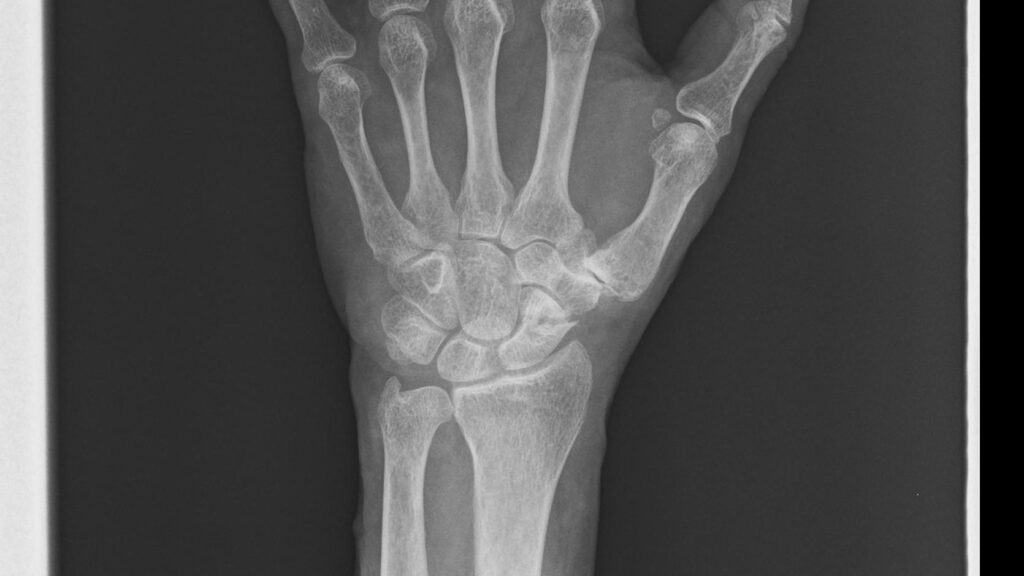

下図は手術前の左手レントゲン写真で、中央の船状骨が砕けている様子が見える。

以下の5枚は再発後、手術直前に撮影されたレントゲン写真である。正面像では舟状骨遠位部に骨折線が見え、斜位像および側面像では骨片のずれが明確に確認できる。

/レントゲン写真を角度を変えて5枚撮影